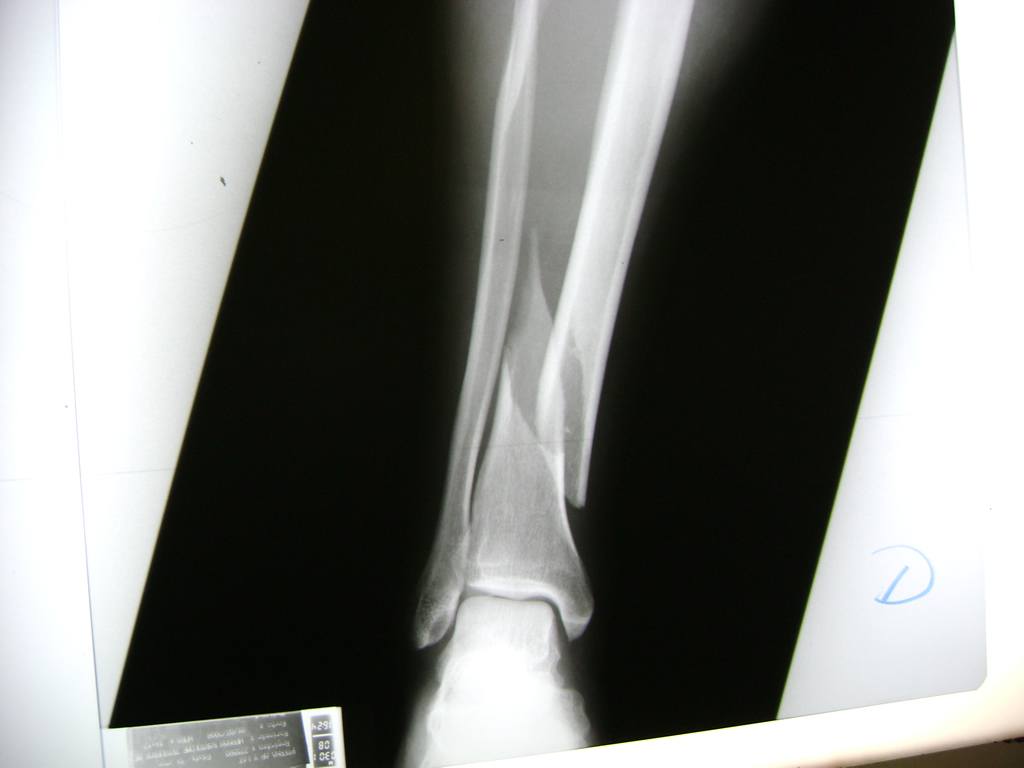

Cirugias en El Salvador - Perone y Tibia

La mayor parte de las roturas implican a la parte proximal del hueso (parte del hueso próximo a la rodilla) o a la parte distal (parte del hueso cerca del tobillo).

Debido a la fina cobertura de piel que recubre la tibia y el peroné, las fracturas generalmente son abiertas, es decir, el hueso roto rasga la piel, atravesándola. Las fracturas de tibia y peroné generalmente se producen por un fuerte impacto o torsión.